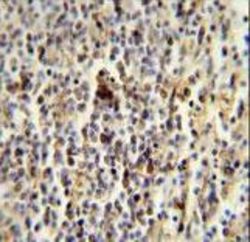

- Experimental details

- CD1E Antibody immunohistochemistry of formalin-fixed and paraffin-embedded human spleen followed by peroxidase-conjugated secondary antibody and DAB staining.